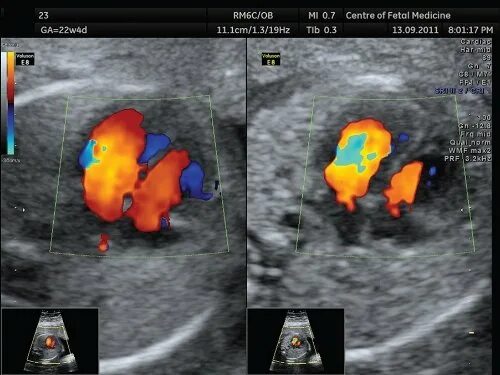

Сердце визуализация затруднена